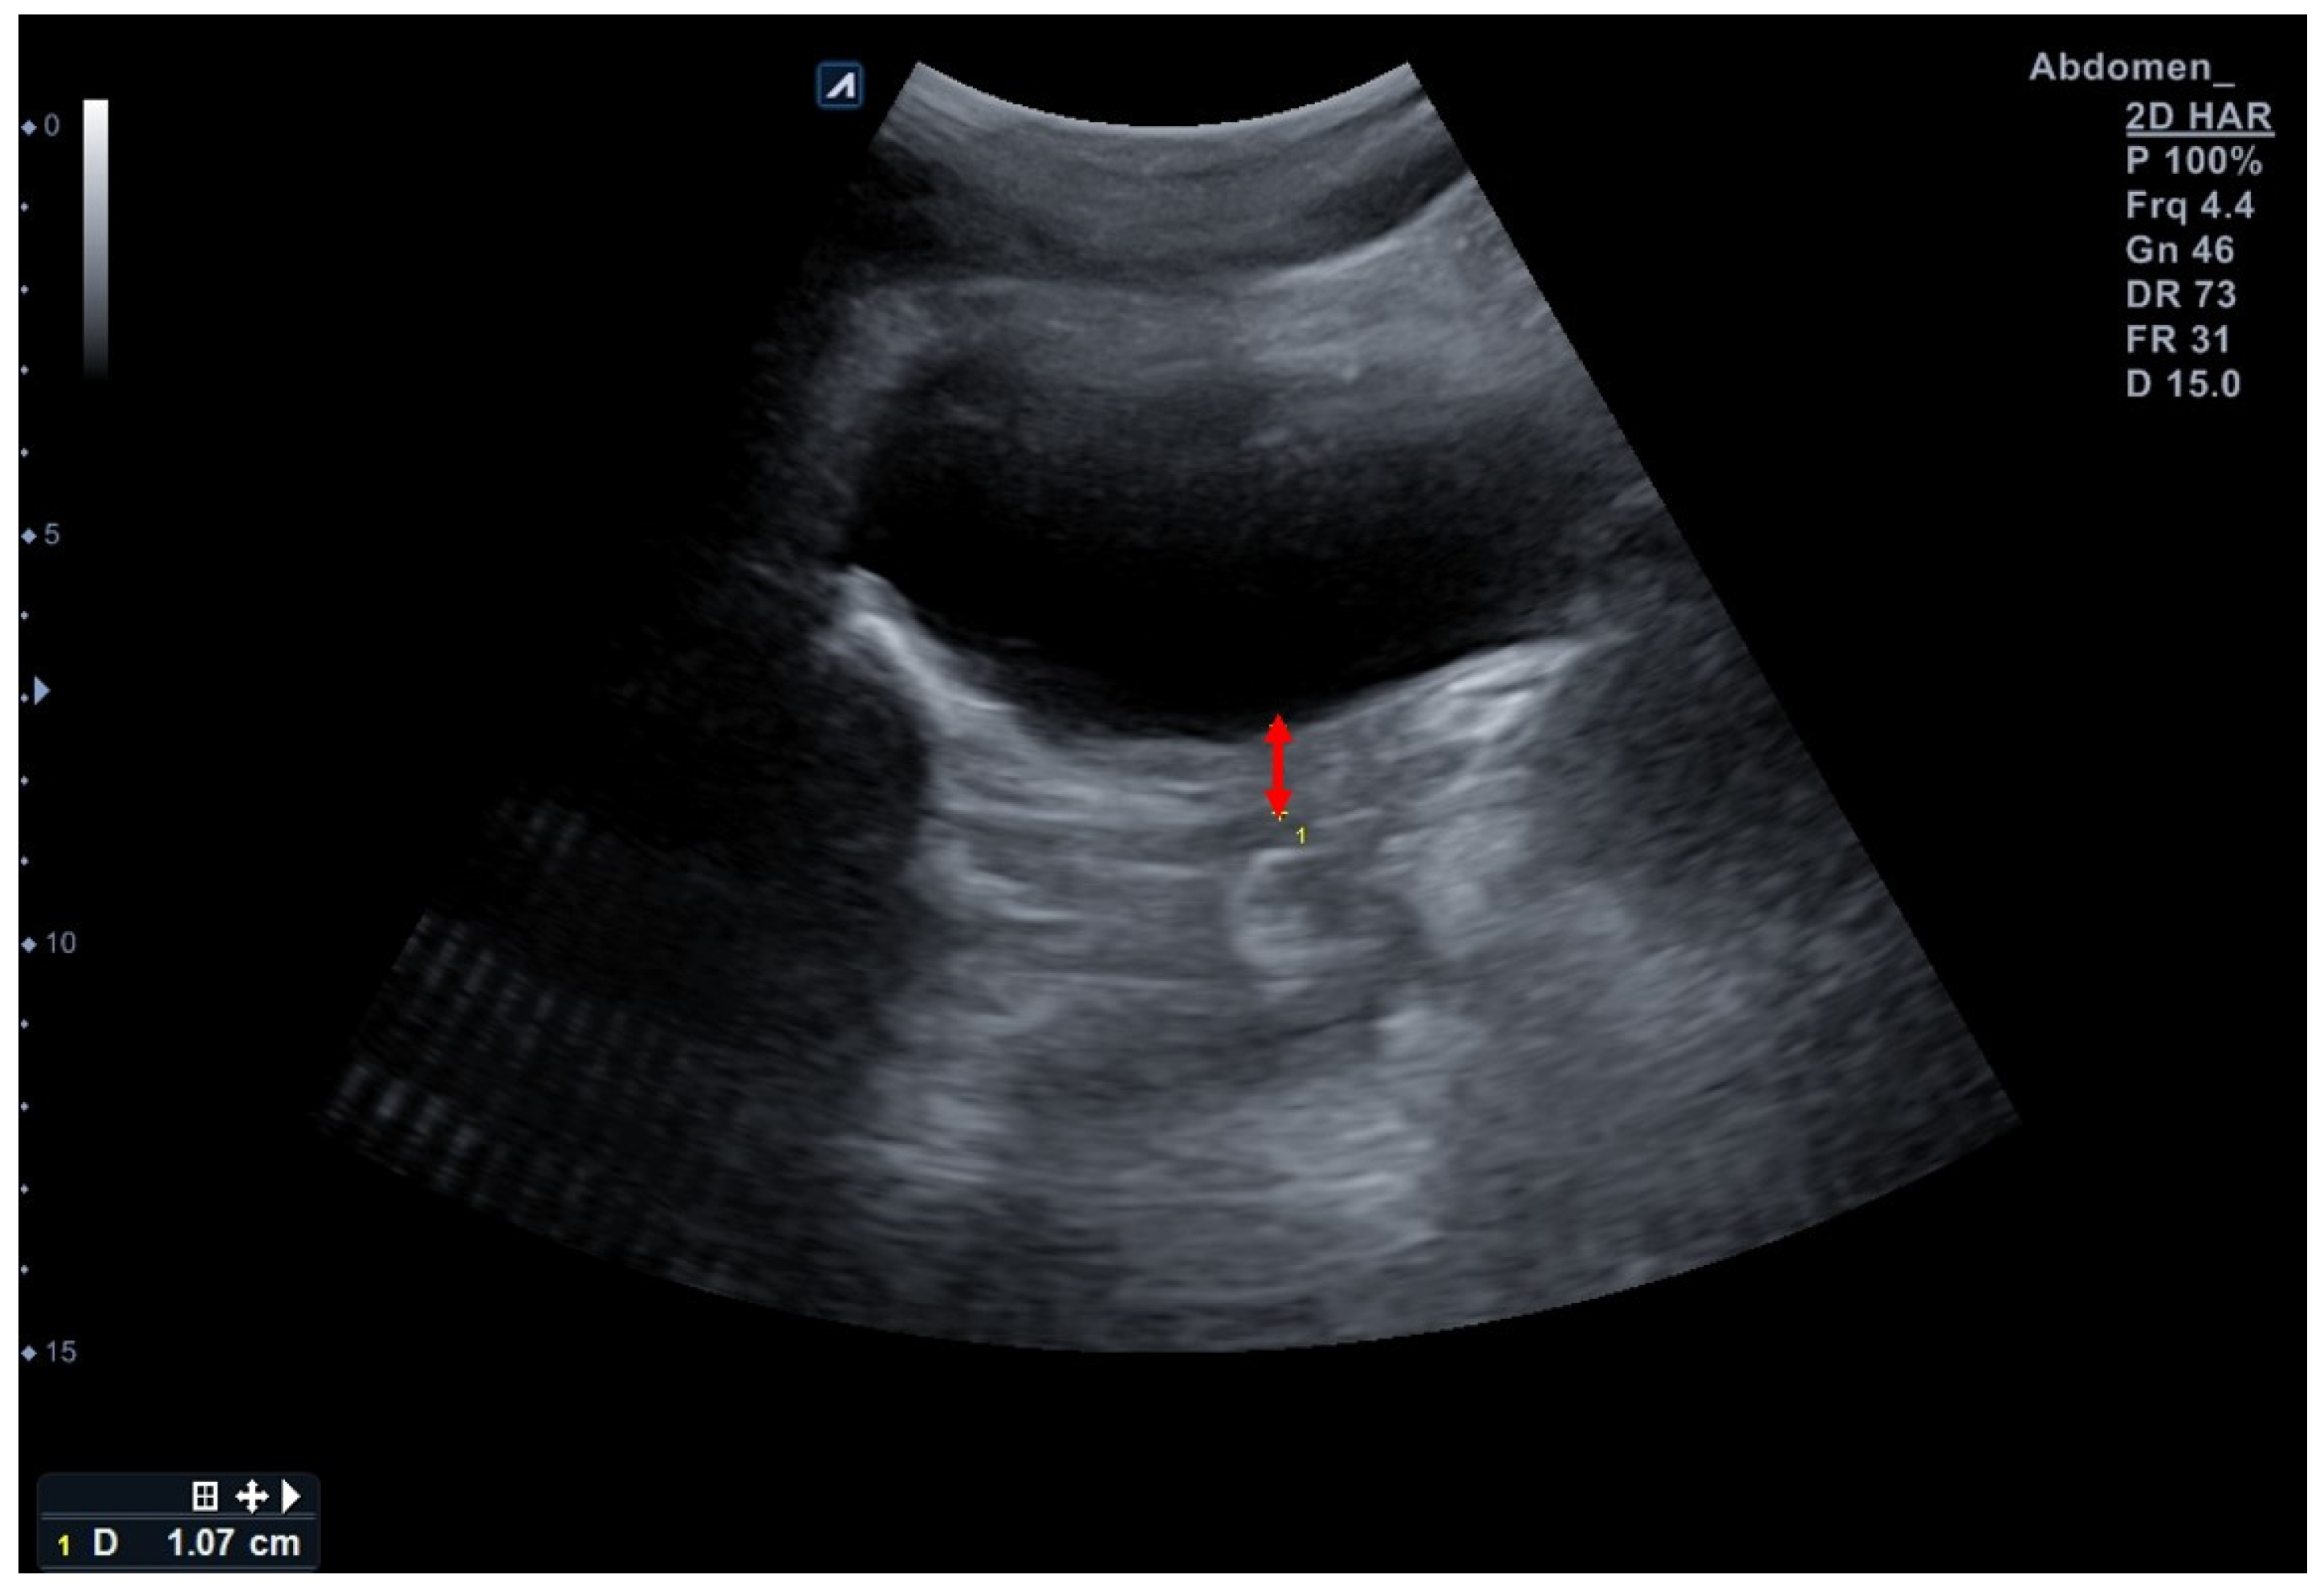

2.5.2. Bladder Base Displacement Using TAUS

| Bladder base displacement (mm) | 7.2 ± 2.5 | - | |